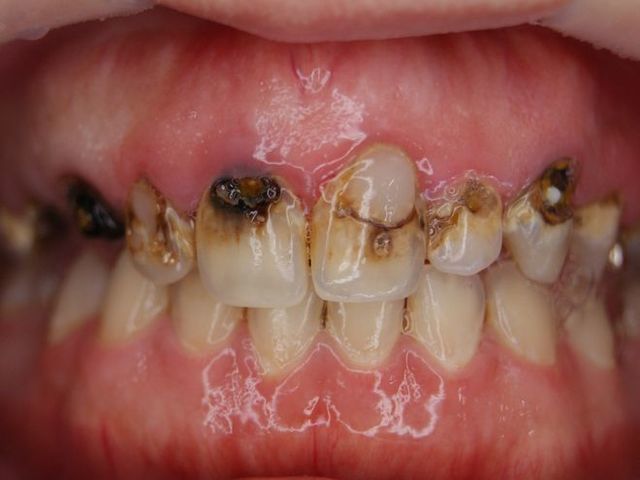

虫歯の治療

C処置術前.jpg

c処置術後.jpg

多発性カリエスです。CRで充填修復しています。出来るだけ歯質を残しています。

同じくCR(コンポジットレジン)で修復。保険の範囲内で治療できます。